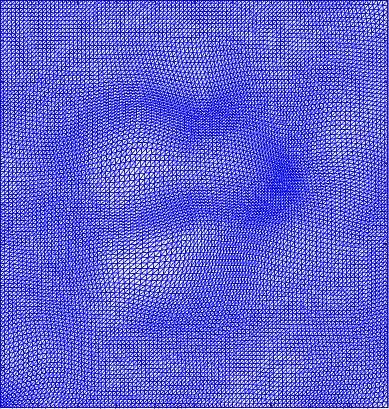

Figure 4 shows the visualisation of Figure 3 mappings in the form of grids. Let and be the Beltrami coefficients of the registration maps from the reference frame to the ground truth frame in Figure 3(a) and the perturbed frame in Figure 3(b) respectively. Figure 4(a) shows the mapping associated to Beltrami coefficient , and Fig 4(b) shows the mapping associated to BC . From Figure 4(c) and Fig 4(d), we can see that our method successfully restored the normal and abnormal deformation. Figure 4 serves as evidence that our decomposition is meaningful, in the sense that our method does not blindly return a Beltrami Descriptor with certain periodicity, but the decomposed descriptor does carry our desired information to recover the deformation to a large extent.